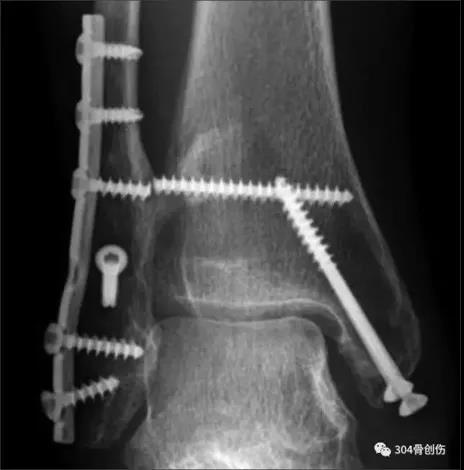

术后DR

固定方法1、螺钉固定:在下胫腓联合上方1~3cm处,用1~2枚3.5mm皮质骨螺钉平行关节面向前倾斜30贯穿2层腓骨及1层胫骨皮质,在踝关节轻微背屈位固定,不做加压。2、胫腓钩(Link)3、endobutton,可吸收钉等

术前DR